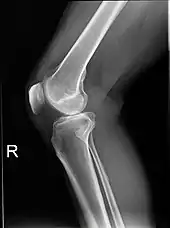

Plain radiograph of the right knee

Projectional radiography is the practice of producing two-dimensional images using X-ray radiation. Bones contain a high concentration of calcium, which, due to its relatively high atomic number, absorbs X-rays efficiently. This reduces the amount of X-rays reaching the detector in the shadow of the bones, making them clearly visible on the radiograph. The lungs and trapped gas also show up clearly because of lower absorption compared to tissue, while differences between tissue types are harder to see.

Projectional radiographs are useful in the detection of pathology of the skeletal system as well as for detecting some disease processes in soft tissue. Some notable examples are the very common chest X-ray, which can be used to identify lung diseases such as pneumonia, lung cancer, or pulmonary edema, and the abdominal x-ray, which can detect bowel (or intestinal) obstruction, free air (from visceral perforations), and free fluid (in ascites). X-rays may also be used to detect pathology such as gallstones (which are rarely radiopaque) or kidney stones which are often (but not always) visible. Traditional plain X-rays are less useful in the imaging of soft tissues such as the brain or muscle. One area where projectional radiographs are used extensively is in evaluating how an orthopedic implant, such as a knee, hip or shoulder replacement, is situated in the body with respect to the surrounding bone. This can be assessed in two dimensions from plain radiographs, or it can be assessed in three dimensions if a technique called '2D to 3D registration' is used. This technique purportedly negates projection errors associated with evaluating implant position from plain radiographs.[98][99]